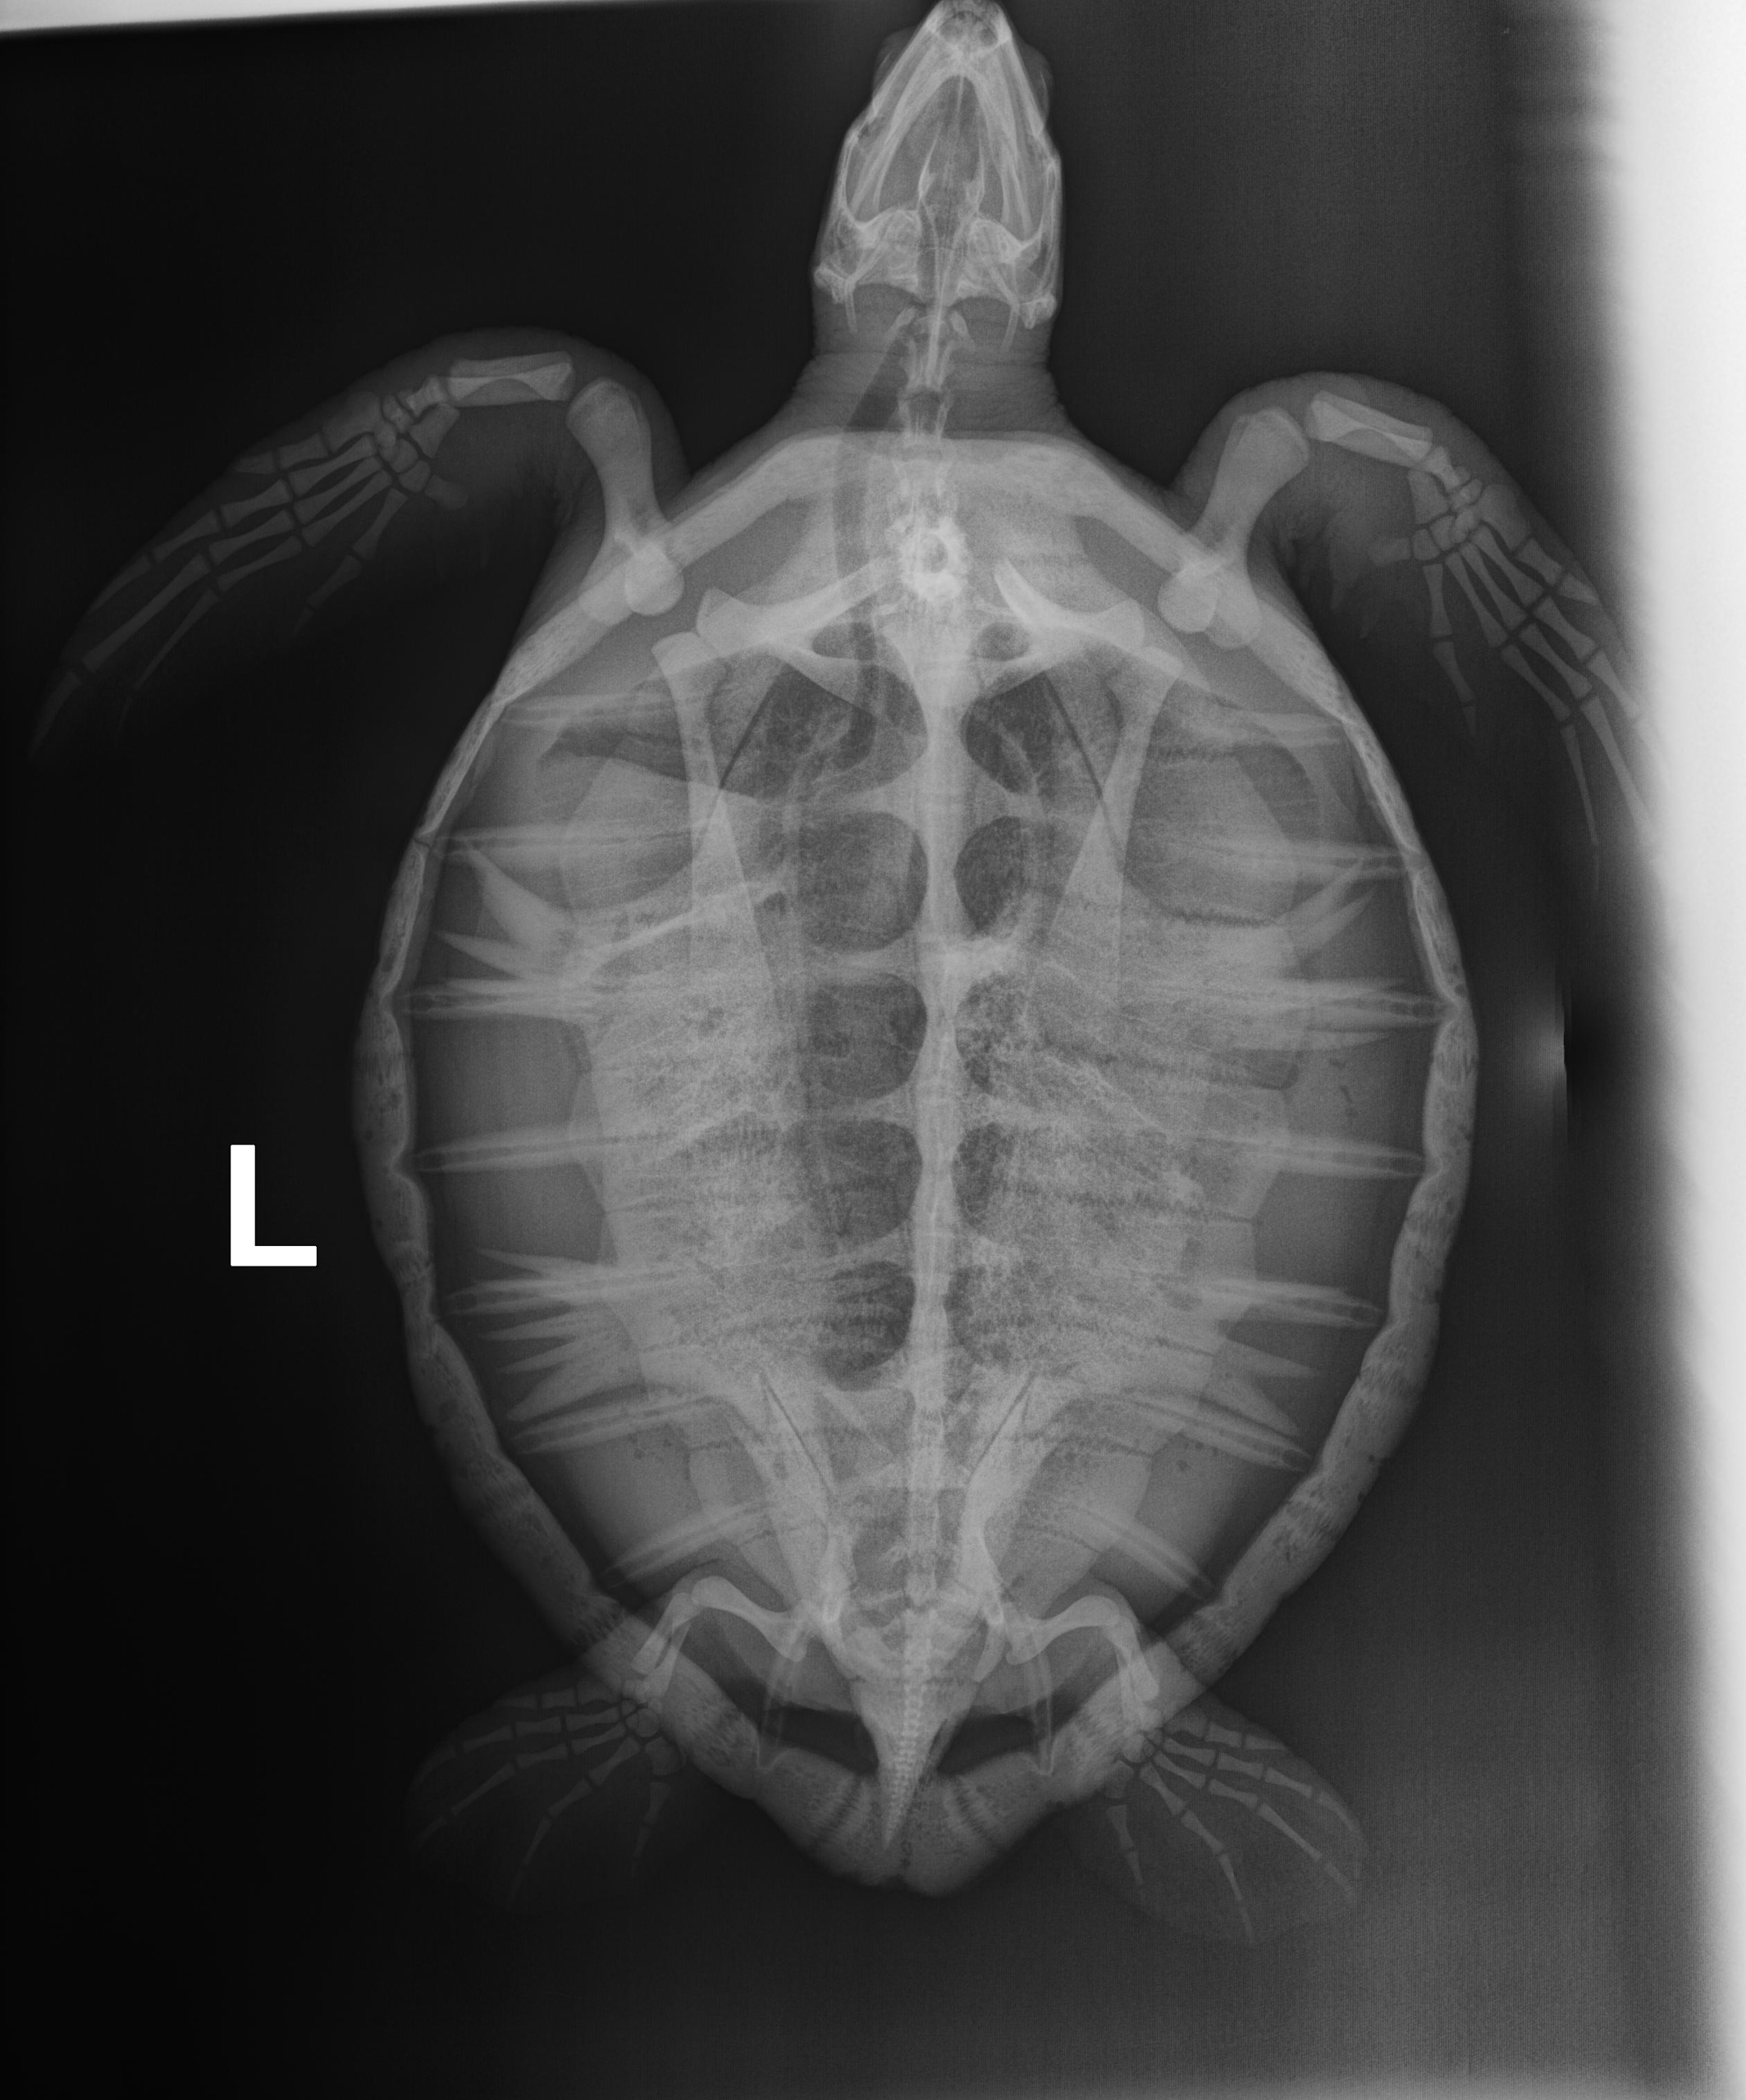

5.8 lb non-FP juvenile green

Moderate abrasions on the plastron and the carapace. Minor abrasions to the flippers and on the head. Possible, healed old hook wound in the right front flipper.